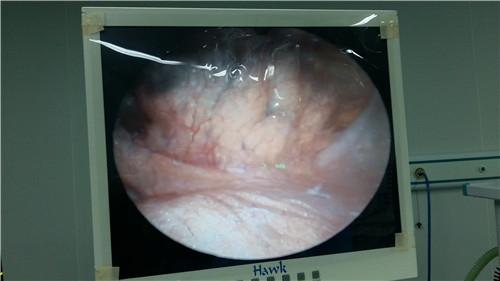

除了这些临床表现,到医院就诊时,医生会对膝关节进行详细的体格检查,比如关节间隙的压痛、过伸试验、过屈试验和半月板旋转试验等,必要时做MRI检查以确诊。